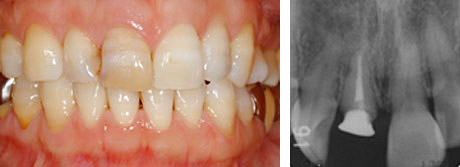

上顎前歯部のインプラント

この症例は、折れてしまった前歯をインプラントで治療した例です。

治療前:右上前歯の破折で患者さんは来院されました。

残念ながら、患歯は治療することができず抜歯になりました。以前は、このような状態をブリッジで治していましたが、きれいなとなりの歯を削ることなくこの状態を治す方法として、インプラントは優れています。

治療後:天然歯と見分けがつかないぐらいに治っています。